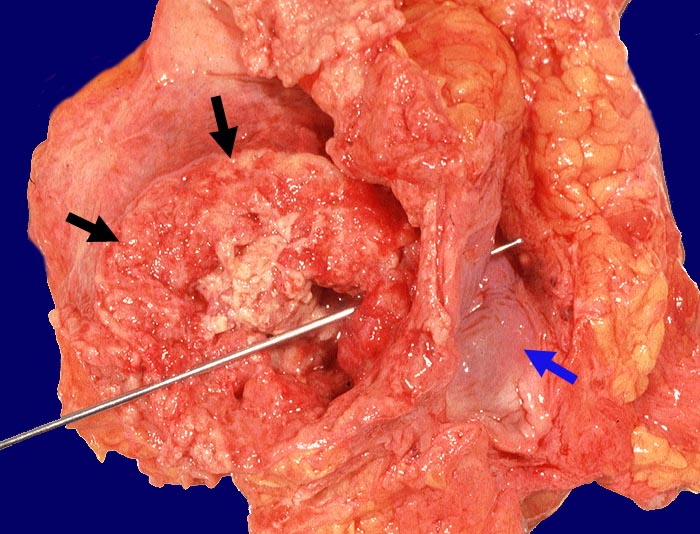

PathoPic – image database / PathoPic ID 955 - Harnblasenkarzinom mit vesikovaginaler Fistelbildung

Harnblasenkarzinom mit vesikovaginaler Fistelbildung

Polypöser Tumor der Harnblase. Die Sonde steckt in der tumorbedingten vesikovaginalen Fistel. Rechts ist die graue glatte Vaginalschleimhaut erkennbar.

Wenig differenziertes Urothelkarzinom. Tumordurchmesser 10cm. Infiltration des perivesikalen Fettgewebes mit vesikovaginaler Fistelbildung.